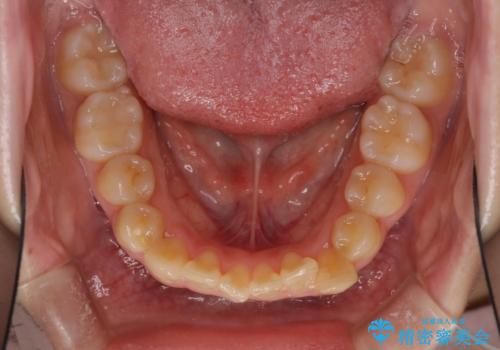

- デコボコと飛び出した前歯を治したいとのことで来院された患者様です。

ゴムかけを活用して上顎歯列全体を後方移動し、IPR(歯と歯の間を削る)によってデコボコが解消するように設計し、インビザラインにより治療を行うこととしました。

後方移動に際し、上下顎の親知らずは4本とも抜歯することとしました。